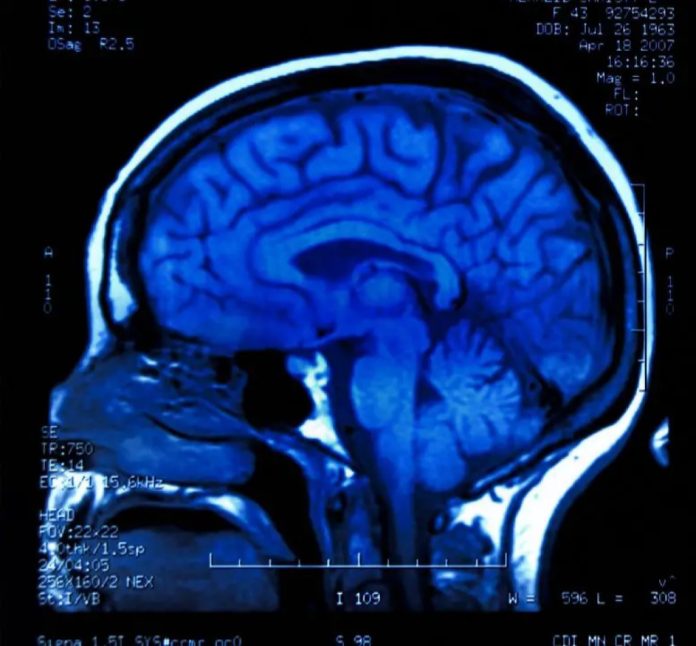

Il cervello umano, con le sue complessità che vanno dalle reti neurali alle funzioni e strutture biologiche fondamentali, rimane sfuggente nel rivelare i suoi segreti. Tuttavia, i recenti progressi nella neuroimaging e nella biologia molecolare hanno fornito agli scienziati la possibilità di studiare il cervello vivente con dettagli senza precedenti, rivelando molti misteri precedentemente sconosciuti.

Lo studio si concentra sulle membrane che racchiudono il cervello, che creano una barriera dal resto del corpo e lo mantengono immerso nel liquido cerebrospinale. La comprensione tradizionale di ciò che viene chiamato collettivamente lo strato meningeo, una barriera composta da singoli strati noti come dura, aracnoide e materia pia.

Il nuovo strato scoperto dal gruppo di ricerca con sede negli Stati Uniti e in Danimarca divide ulteriormente lo spazio al di sotto dello strato aracnoideo, lo spazio subaracnoideo, in due compartimenti, separati dallo strato appena descritto, che i ricercatori hanno chiamato SLYM. Mentre gran parte della ricerca nel documento descrive la funzione di SLYM nei topi, viene riportata anche la sua effettiva presenza nel cervello umano adulto.